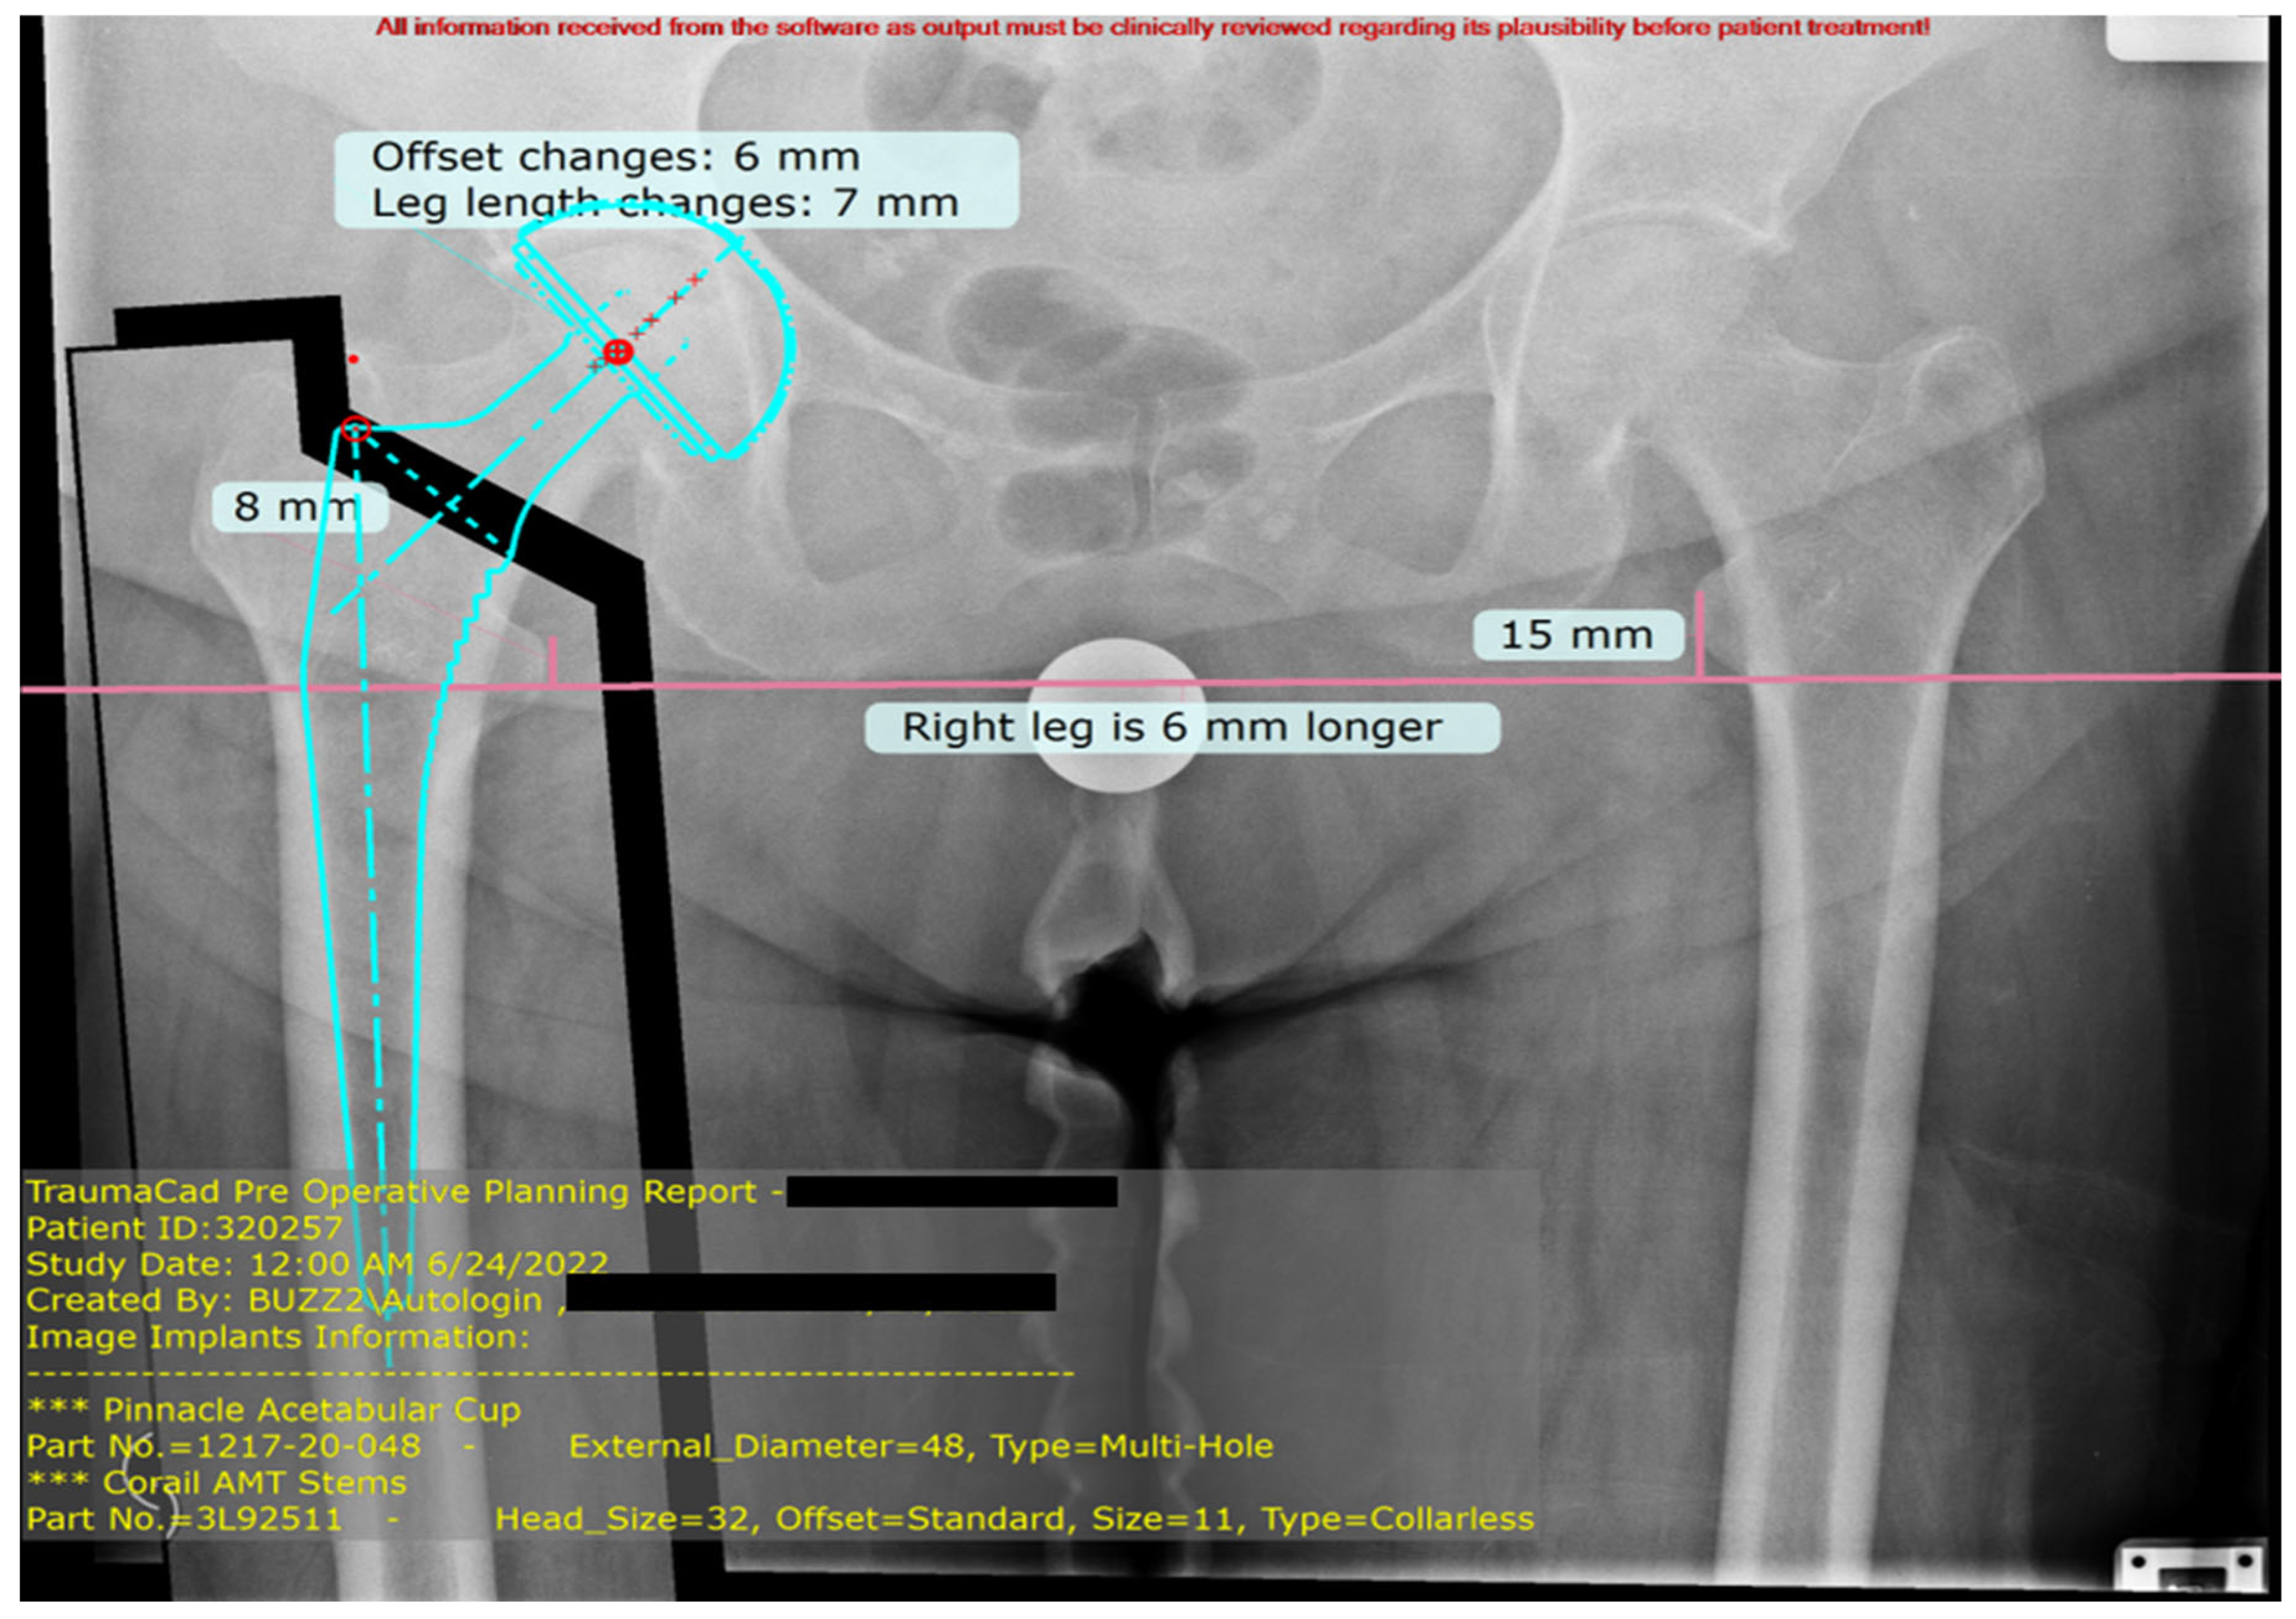

2.3. Preoperative Templating Protocol